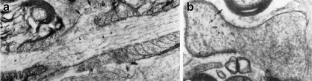

Fig. 2